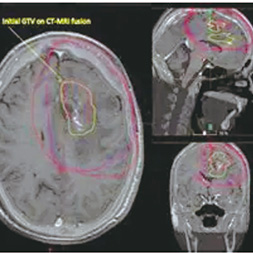

FET-PET在诊断复发性胶质母细胞瘤方面的特异性CE-T1MRI。为了评估基于FET-PET的靶体积勾画与CE-T1MRI相比,是否能改善拟再次放疗的复发性胶质母细胞瘤患者的结局,该项在德国15个放射肿瘤中心进行的、多中心、开放标签、平行分组随机研究(GLIAA/NOA-10 ARO2013-01)纳入≥18岁的、卡氏评分≥60%的、大体下WHO分级为4级(1~6 cm)的、复发性胶质母细胞瘤患者,等比分予基于FET-PET或CE-T1MRI的靶体积勾画,随后再次放疗(39 Gy/13 f),并按照首次放疗时间、既往化疗、肿瘤直径、MGMT状态和计划的化疗进行分层。